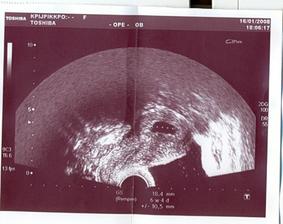

16/1 - 1. kontrola u Dr.,

od 18/1 doma na neschopence, Duphaston

30/1 - 9. týden, mimi je krásné - má ručičky, nožičky, hýbe se,